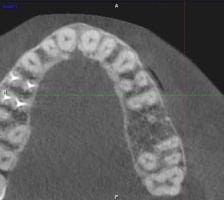

Esta semana me hicieron un tac, porque en la orto y en la radiografía periapical no salía nada. Le adjunto imágenes del mismo, y le agradecería enormemente su opinión.